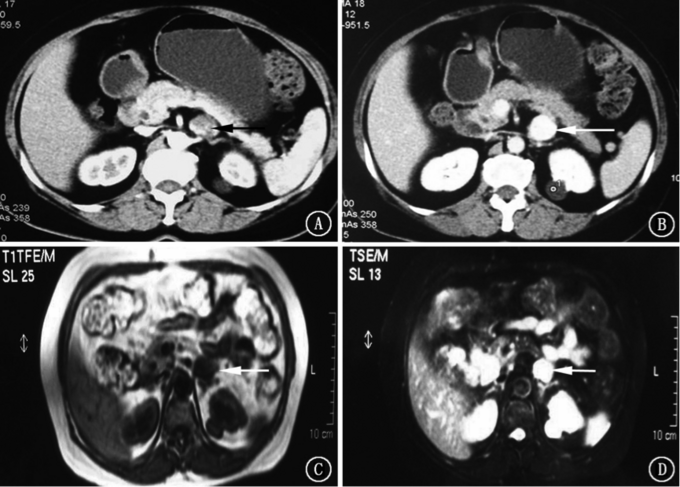

患者,女,62 岁。 因“阵发性血压升高10 年,加重6 个月,发现左肾上腺占位2 个月”入院。 患者10 年前无明显诱因开始出现发作性血压升高,发作时伴全身震颤、心悸、大汗,多于凌晨4 ~5 点发作, 血压最高达175/55 mmHg,先后服用硝苯地平、厄贝沙坦片等,血压可以控制在150/60 mmHg 左右。6 个月前症状加重,发作频率增加。患者因胃痛于当地 医院就诊,B 超检查示左侧肾上腺区低回声占位。腹部增强CT 检查:左侧肾上腺前方不规则肿块,大小约4.5 cm×2.5 cm×3.9 cm,与左侧肾上腺体部分界不清,增强扫描动脉期边缘强化,门脉期造影剂向内充填,延迟期为均匀高密度,腹膜后占位考虑良性病变可能。腹部MR 检查:腹主动脉左前方肿块,边缘清晰光滑,T1WI 呈低信号,T2WI 呈明显高信号,腹膜后占位性病变考虑为嗜铬细胞瘤可能(图1)。